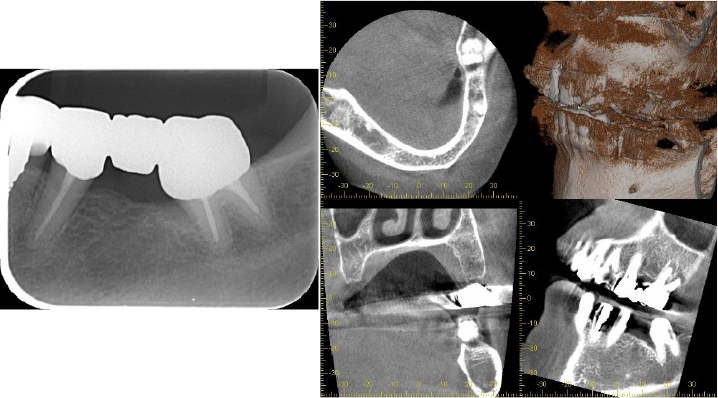

デンタルおよびCT所見

before before |

after after |

術前 術前 |

術後8カ月 術後8カ月 |

歯周病により失われた歯槽骨が骨様組織により改善されているように思われます。

右の下奥歯には深い歯周ポケットが残っています。

レントゲン写真では矢印の位置ぐらいには骨がありそうに見えますが、CTにて詳しく調べてみると矢印の位置まで歯周病が進行して骨が破壊されていることがわかります。

患者さんと相談した結果、歯周組織再生療法を希望されたため、施術させていただくことになりました。

術直後のレントゲン写真です。

術後8か月 術後8か月 |

術後15か月CT所見 術後15か月CT所見 |

術前 術前 |

術後15か月CT所見 術後15か月CT所見 |

術前で破壊されていた部分に骨の再生が認められるため、黒かった部分が白くなっていることがわかります。

再生療法時 骨が失われている部位 骨が失われている部位 |

再生療法後 再生した部位 再生した部位 |

| 失われていた骨の再生が認められます。 | |

CT所見で見られたのと同様に再生療法を行った部位にみられた骨欠損は骨様組織にて満たされていることがわかります。